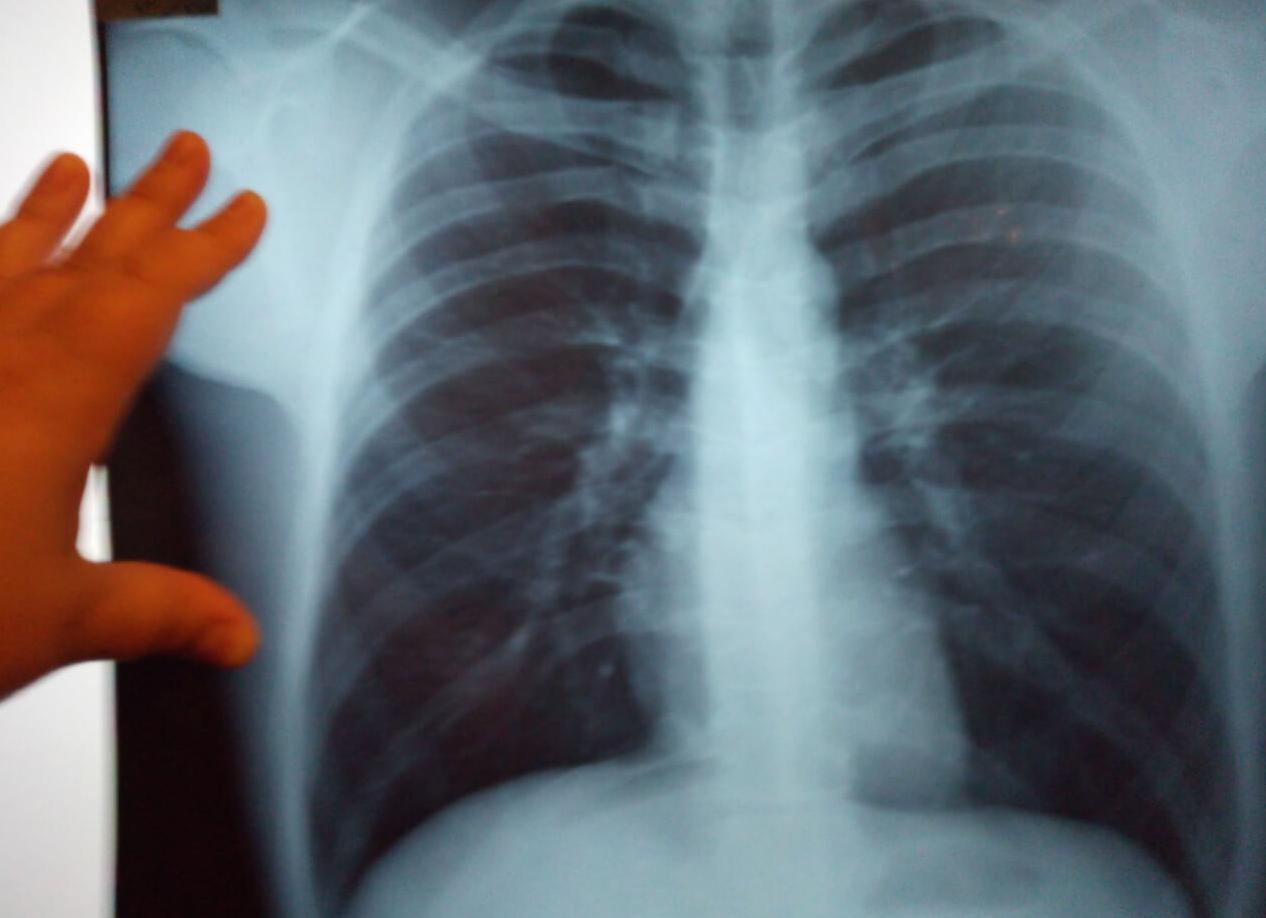

Снимок легких здорового человека выглядит типично:

- Легочные поля, расположенные с обеих сторон грудной клетки.

- Сердечная тень и грудина – в центре рентгенограммы.

- Ключица – в верхней части.

- Купола диафрагмы – снизу под легочными полями.

- Линейные тени ребер над проекцией легких.

На фото врач-рентгенолог оценивает следующие структуры:

- Мягкие ткани.

- Костно-суставная система.

- Диафрагма.

- Средостение.

- Реберно-диафрагмальные синусы.

На рисунке приведена нормальная рентгенограмма легких. Запомните ее вид. Если на снимке обнаружите дополнительные пятна, которые отличаются от вышеприведенного фото, скорее всего, такая картина будет отражать патологический процесс.

Рентген легких здорового человека дает возможность врачу оценить мягкие и костные ткани, структуры границ. При отсутствии каких-либо негативных изменений в легких нормальный снимок здорового пациента будет выглядеть как на фото сверху. Снимок больного человека будет отличаться наличием затемнений, утолщений, просветлений, которых нет на снимке здорового.

Рентгеновский снимок лёгких здорового человека обладает следующими характеристиками:

- полученное изображение является однородным, не имеет затемнений;

- лёгкие расположены в правильной позиции, имеют 5 хорошо различимых долей (их величина определяется возрастом пациента);

- в структуре лёгочной ткани отсутствуют видимые волокна;

- корни правого и левого лёгкого обладают чёткой структурой, их размеры не выходят за пределы нормы;

- мягкие ткани однородные, в них нет рубцов, опухолевидных образований, «карманов» с газом, жидкостью.

Флюорография здорового человека демонстрирует хорошо обозначенные лёгочные поля и купола диафрагмы под ними. В верхней части снимка хорошо просматриваются ключицы, в центре – грудина и тень от сердечной мышцы, над проекцией лёгких видны линейные тени рёбер.